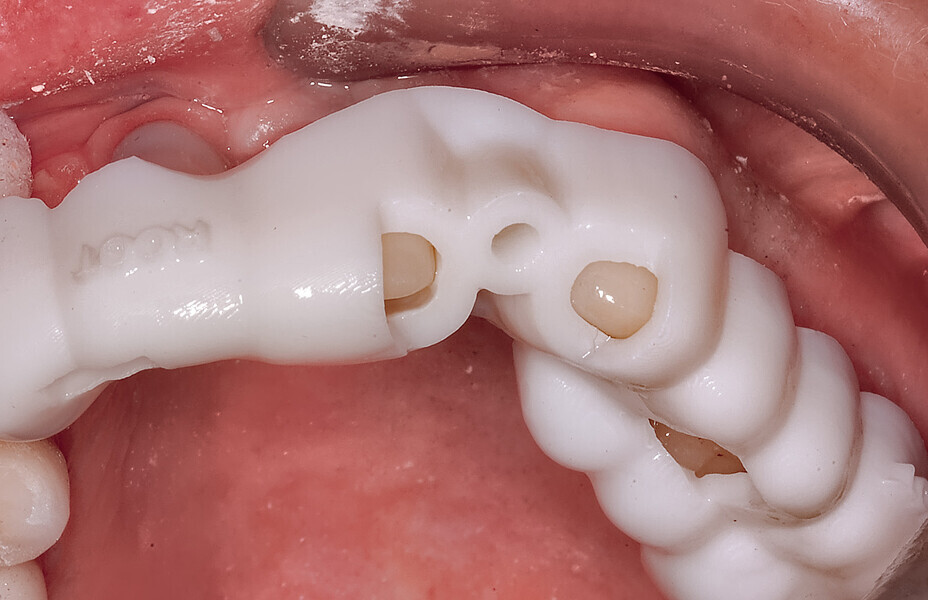

Fig. 11: The stackable tooth-borne guide and the three other separate components.